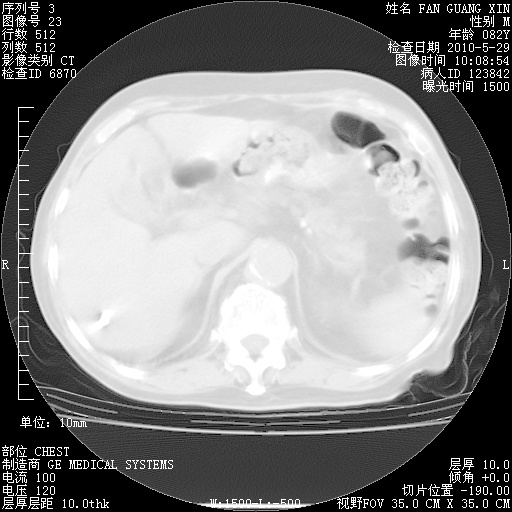

治疗3周后的肺部CT纵隔窗

再治疗10天后的肺部CT